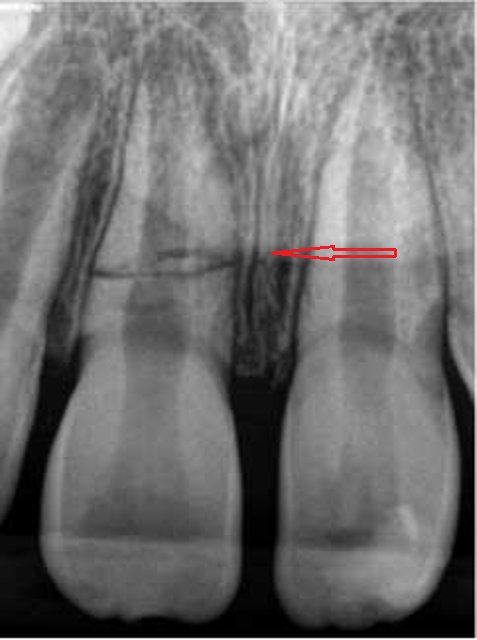

Daimi dişlərin travmatik zədələnmələri uşaq və yeniyetməlik dövründə olan şəxslərdə çox tez-tez rast gəlinir. Tac qırılmaları və lüksasiya travmalar içərisində ən çox rast gəlinənlərdir. Ancaq müxtəlif kliniki hallarda digər zədələnmə formaları da aşkar edilə bilir.

Doğru diaqnostika, müalicə planlaması və sonrakı dönəmdə izləmə uğurlu müalicəyə aparan ən başlıca faktorlardır. Diş travmaları və yaralanmaları tək diş bölgəsini əhatə edən məhdud, eyni zamanda çoxsaylı diş bölgəsini və çənənin alveol darağını əhatə edəcək qədər yayılmış formada rast gəlinə bilir. Çoxsaylı diş zədələnmələrində çox zaman fərqli dişlərdə fərqli növ zədələnmə şəkili aşkar edilə bilir ki, bu da hər bir dişə individual yanaşma və müalicə metodu tələb edir.